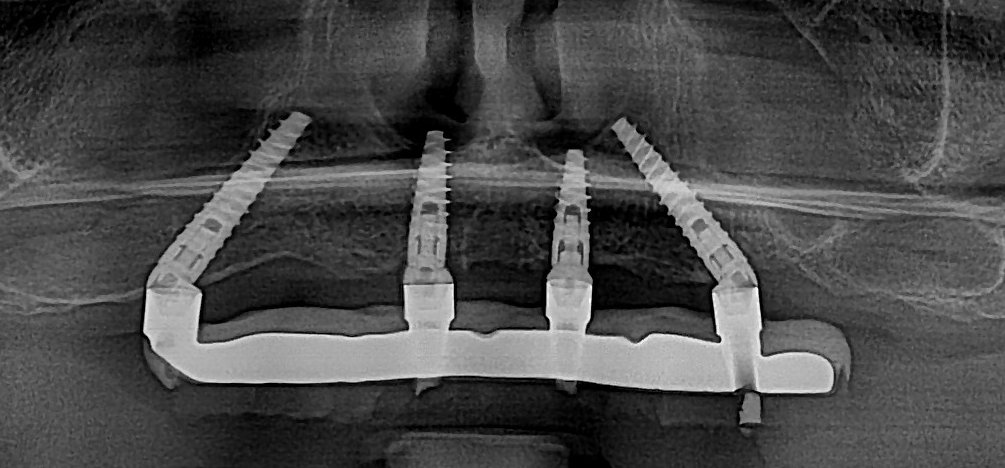

Proteza provizorie este realizată pe un schelet metalic, care îi oferă rezistență și rigiditate, peste care este aplicat un strat de PMMA frezat. Pe radiografie se poate observa clar scheletul metalic ce susține întreaga lucrare.

Proteză montată imediat după procedură